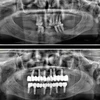

Implant tedavisi